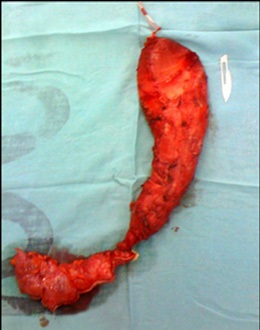

Of the total, 3 corresponded to the male sex and 4 to the female sex. The average age was 54.7 with a range of 35 to 66 years. One case corresponded to a megaesophagus of Chagasic origin, and the other 6 cases were due to recurrence of the Heller-Dor myotomy, which was treated with endoscopic dilations. The treatments performed were: 1 laparoscopic transhiatal esophagectomy and a minimally invasive esophagectomy in the prone position (Figure 2) 4 esophagus ardioplasty procedures, as described in Figure 3, and 1 case of resection of the esophagogastric junction and Roux-en-Y bypass.

Figure 2: Megaeasophagus.